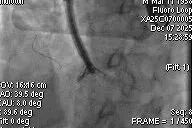

After general anesthesia, the patient underwent jugular vein puncture to establish access. An 18Fr delivery sheath was advanced over a super-stiff guidewire to the mid-to-lower right atrium. Under ultrasound guidance, the delivery system was introduced. A 14T K-Clip® and a 16T K-Clip® device were implanted at the postero-septal commissure annulus and the antero-posterior commissure annulus, respectively. The angle between the device and the annular plane was adjusted through controlled flexion and rotation to orient the device tip toward the target site. Using ultrasound MPR mode, the anchor component was advanced into the annulus. After traction confirmed stability, the clip arms were opened and apposed to the annulus. The anchor component was then retracted to close the clip arms, achieving annuloplasty. The effect was evaluated as satisfactory, and the clip components were deployed.

Delivery system entering RA via SVC

- Optimal fluoroscopic projection: Tricuspid short axis CAU8LAO60.